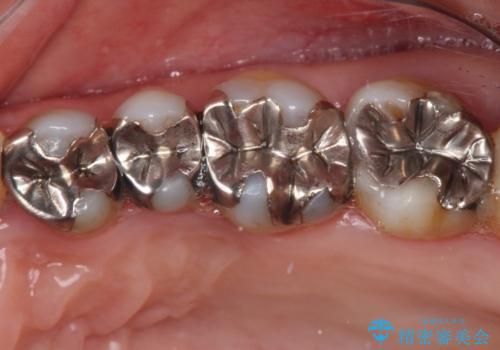

- 奥歯の銀歯をセラミックの白い歯にして、しみる症状も改善したいとのことで来院された患者様です。

知覚過敏の症状が強い歯と、銀歯の範囲や銀歯の下のむし歯が大きい歯は、インレー修復では対応が難しいためオールセラミッククラウンで、インレー修復で対応が可能な歯ではセラミックインレーにて修復することとしました。